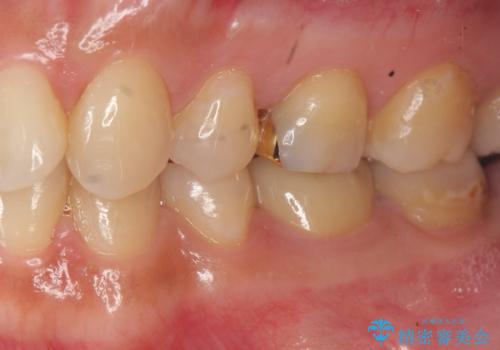

- 11万円(仮歯・ジルコニアクラウン)費用は治療当時の料金となります

口腔内の金属を取り除くことで、健康的で明るい印象となりました。